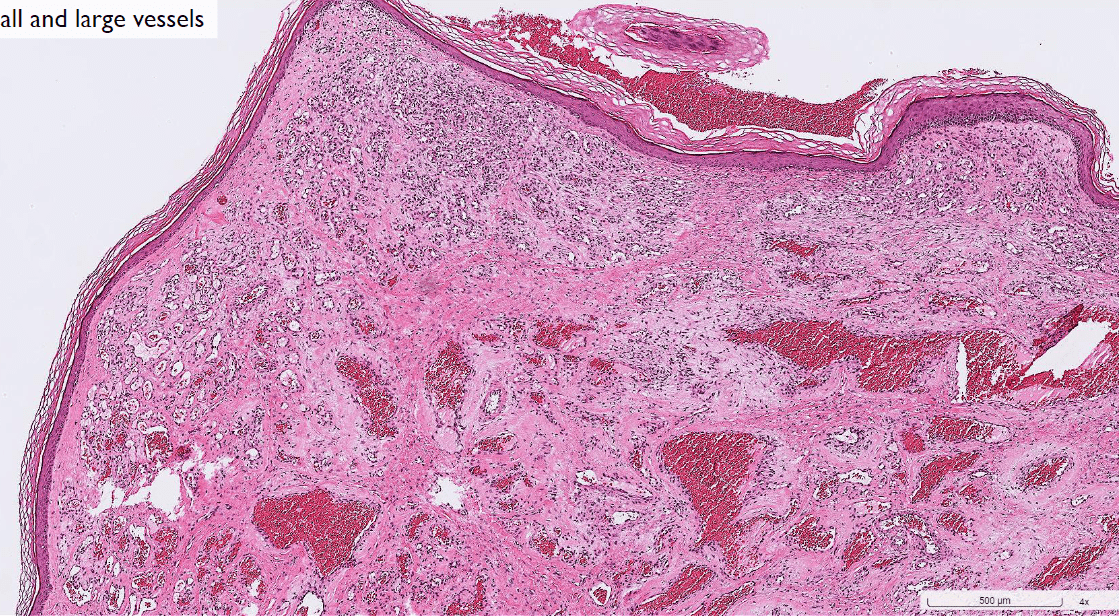

(maybe cavernous or capillary)